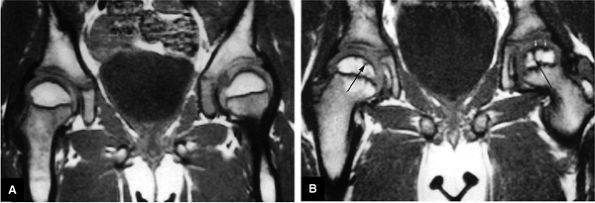

FIGURE 3.92 ● T1-weighted coronal images in LCP. (A) Normal femoral head capital epiphyses. (B) The earliest MR signs of LCP include peripheral irregularity of marrow-fat-containing epiphyseal ossification center (white arrows). Low-signal-intensity foci or linear segments are seen within the right and left ossification centers (black arrows). No subarticular collapse is present, and conventional radiographs are normal (TR, 500 msec; TE, 20 msec).

FIGURE 3.93 ● Coronal T1-weighted images show the spectrum of LCP from (A, B) early to (C, D) late advanced involvement. (A) Small, laterally displaced ossific nucleus with loss of yellow marrow signal intensity (long black arrow) is present early in the disease. Normal contralateral epiphyseal cartilage (curved arrow) and high-signal-intensity marrow (short black arrow) are seen. (B) Complete loss of right femoral epiphyseal marrow signal intensity (arrow) occurs as the disease progresses. (C) Bilateral low-signal-intensity osteonecrotic foci in the femoral epiphysis (arrows) become apparent later in the disease. Articular cartilage is thinner in the older child. (D) Advanced remodeling with coxa plana and coxa magna of the femoral heads (arrows) is indicative of late advanced involvement. (TR, 600 msec; TE, 20 msec.)